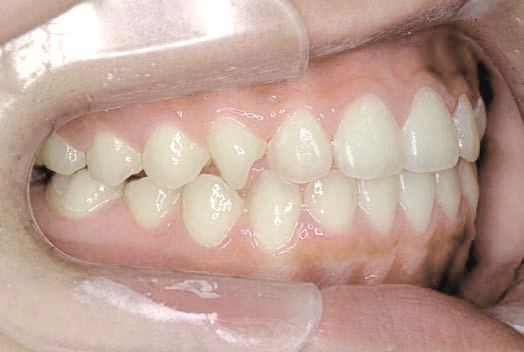

治療を終えて

歯がきれいに生えるためのスペースをしっかり確保することができ、歯並びを乱していたお口のクセも改善されたため、奥歯が生えるスペースを確保することができました。

しっかり噛めるかみ合わせを作ることが、将来の健康につながるので「よく噛む」練習も続けてもらっています。